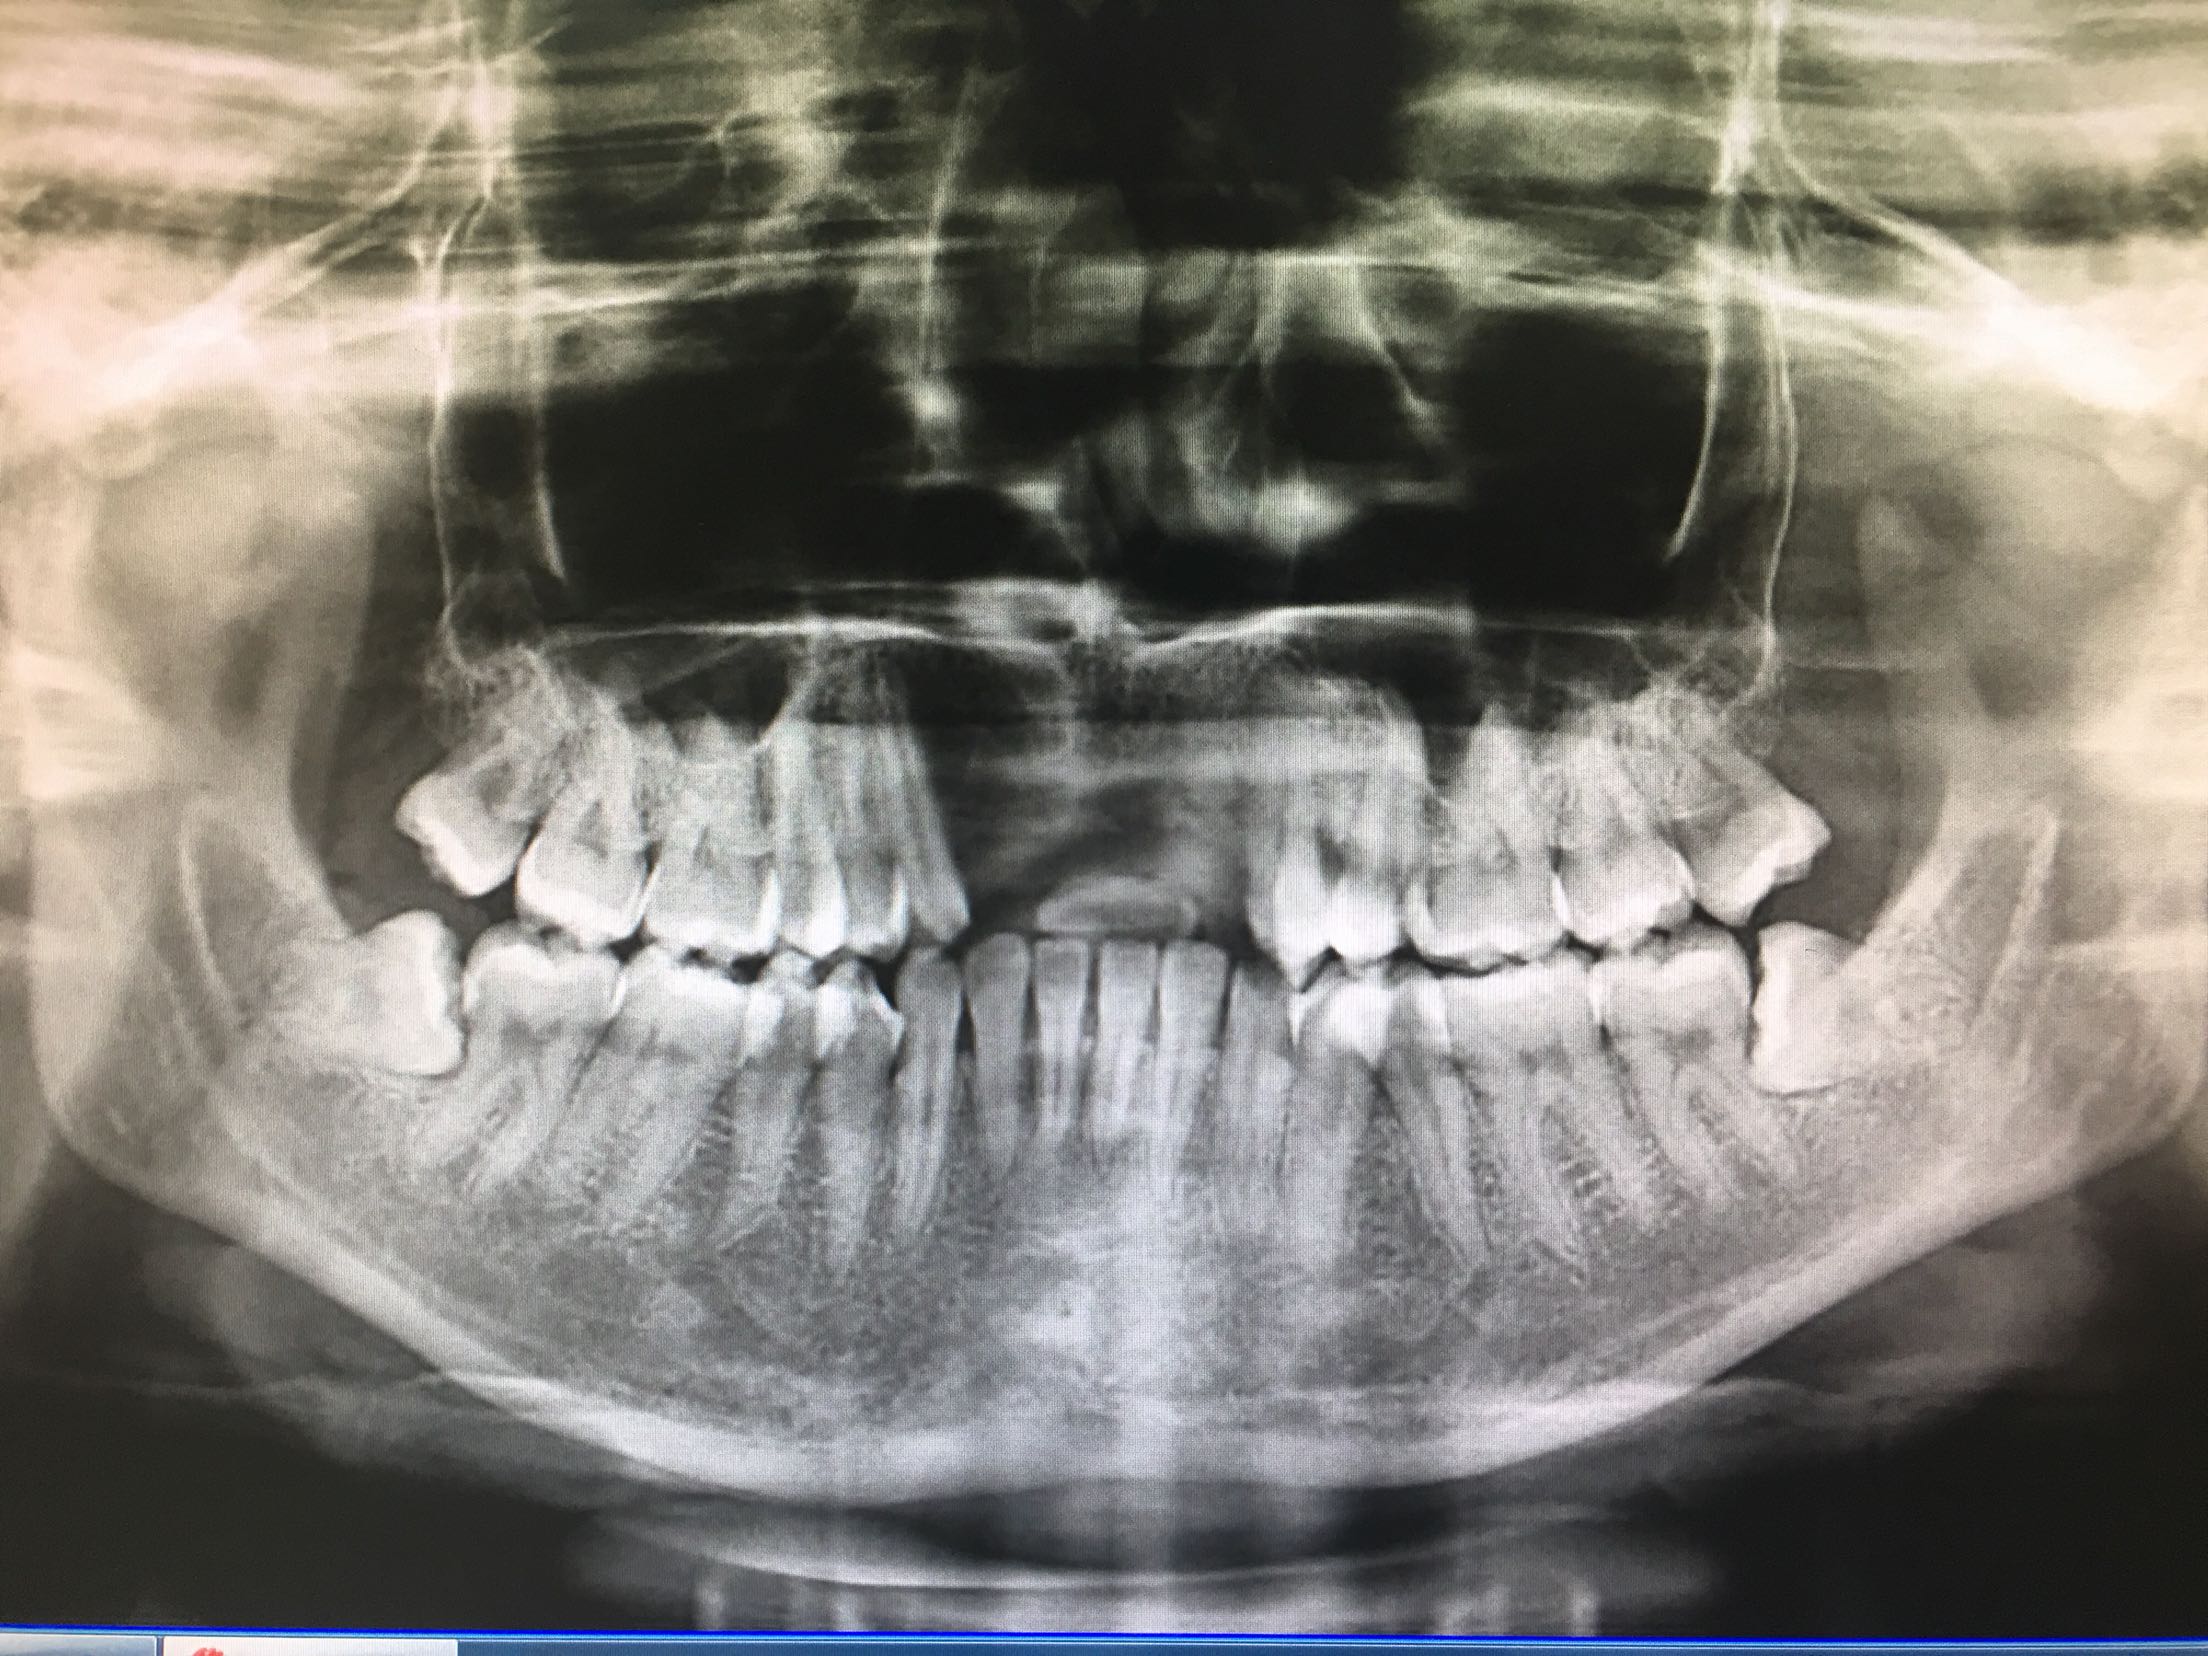

CBCT示11、12、21、22牙缺失,牙槽骨呈刀刃状,38、48牙阻生。